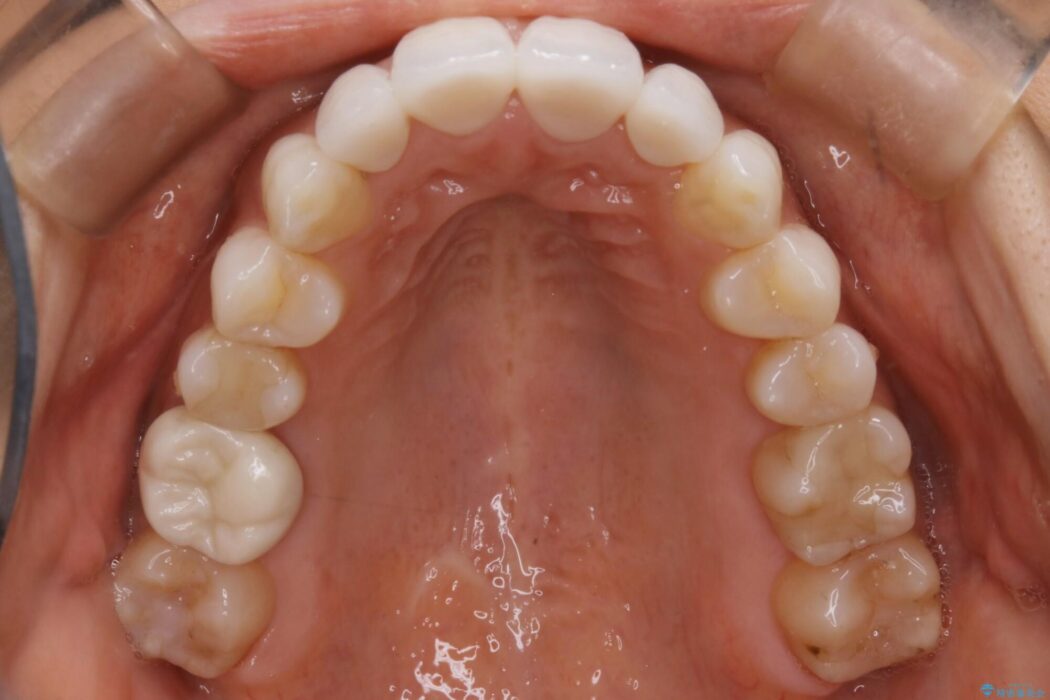

また確認したところ前歯と奥歯にセラミッククラウンで治療した歯があったため、そちらに影響のない範囲内で口腔内全体の噛み合わせが改善されるように歯を動かしていくことになりました。

既定のインビザラインの装着時間を守っていただけたこともあり整ったアーチとなりました。

特に気にされていた噛み合わせは改善されご満足いただけました。